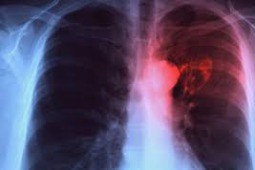

Wyniki pracy zostały opublikowane na łamach czasopisma Mucosal Immunology. Jak informują naukowcy, nowa formulacja szczepionki chroni przed gruźlicą lepiej niż dotychczasowa i nie powoduje żadnych uszkodzeń w tkance płuc. Nadal badane jest jej bezpieczeństwo oraz efektywność i jeśli zostaną udowodnione nowa szczepionka będzie mogła być podawana bezpośrednio do płuc w formie sprayu poprzez specjalnie zaprojektowane urządzenie podobne do inhalatorów stosowanych w astmie. Obecnie dostępna szczepionka podawana jest w formie zastrzyku w ramię.

Jak działa nowa szczepionka? Wnikające do płuc prątki mają styczność ze sluzówką, która wytwarza enzymy zmieniające antygeny mikrobów. Te ostatnie są z kolei częścią molekuł, z którymi łączą się przeciwciała wytwarzane przez organizm ludzki. Nowa formulacja szczepionki stwarza przestrzeń do odpowiedzi immunologicznej, która omija zmiany w antygenach bakterii. Komórki układu odpornościowego T lepiej mogą zapamiętać tę odpowiedź, rozpoznać bakterię i ją zniszczyć.